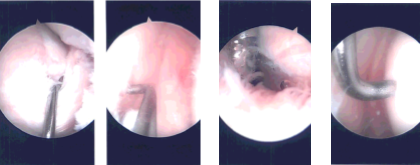

Intraoperative Arthroscopy Images

A left lateral entry portal was made through the and arthroscope was inserted. Medial entry portal was made with the use of spinal needle. Examination of the medial tibiofemoral compartment showed grade 4 osteoarthritic changes of the medial tibial plateau and grade 1 to grade 2 osteoarthritic changes of the medial femoral condyle.

It showed tearing of the medial meniscus in the region of the junction of the body and the posterior horn going into the posterior horn. Debridement of the medial meniscus was done with the use of shaver and biters. Debridement of the cartilage was also done with the use of shaver.

Abrasion chondroplasty of the tibial surface. Examination of the intercondylar notch showed degenerative ACL but not tear. Examination of the lateral tibiofemoral compartment showed no arthritis and no tear.

Examination of the patellofemoral compartment showed grade 2 to grade 3 osteoarthritic changes of the trochlea as well as patella. Debridement of the trochlea and patella was performed with the use of a shaver.

There was extensive synovitis in the suprapatellar region which was debrided with the use of shaver. Histopathology was sent for all the shavings. Final picture was taken and saved.